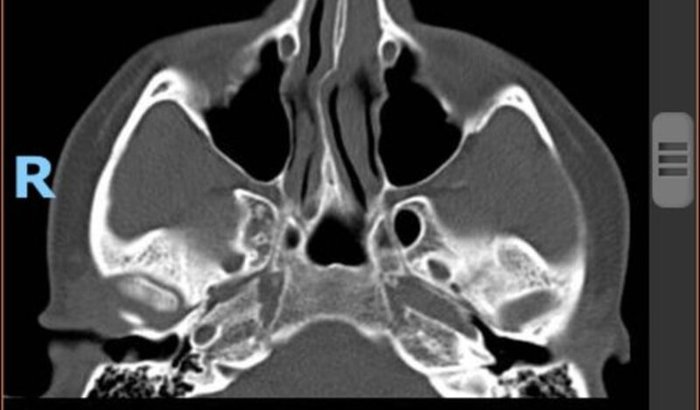

Recentemente passei por um episódio onde a pessoa veio de encontro e bateu acidentalmente a cabeça no meu rosto, e o impacto foi tão forte que caí quase inconsciente. Meu nariz ficou fraturado em vários pontos, e agora preciso de uma cirurgia em até 15 dias, antes que o osso cicatrize errado.

Mesmo com fratura, os médicos explicaram que eu preciso de cirurgia em até 15 dias, antes que o osso cicatrize torto e eu tenha que conviver com dor, dificuldade para respirar e uma futura cirurgia muito mais complicada.Infelizmente, o SUS não está priorizando casos assim no fim do ano, pois muitos médicos entram de férias eu corro o risco de ter que conviver com dor, dificuldade para respirar e esperar meses por uma cirurgia que deveria ser imediata.